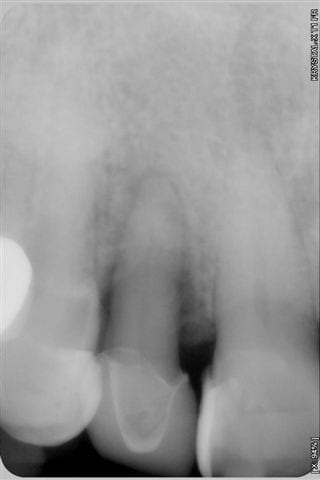

Souvenez vous, il y a 6 mois, je vous ai posté des photos sur un cas de parodontopathie aiguë localisée à la 12, voici les photos et radio 6 mois plus tard, après traitement de la paro au laser diode 980 nm sous bipivone puis H2O2, bio stimulation tous les 15 jours et reconstruction de la couronne en emax avec le CEREC 6 mois plus tard.

Résultat clinique et radiologique plutôt encourageant à 6 mois.

- Dommage que les radios ne soient pas indexées avec leur date, car avec le désordre dans lequel le serveur les met, c'est un peu plus difficile de suivre l'évolution de la guérison (qui n'est pas encore complète apparemment).

- J'espère que tu as bien évalué la vitalité pulpaire car celle-ci n'est peut être pas au top de son potentiel après tout ça.